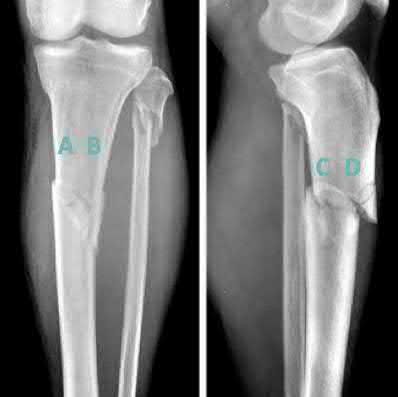

Question 19:

A 28-year-old male sustains a closed comminuted tibial shaft fracture. Two hours post-injury, he develops severe leg pain unyielding to narcotics. His blood pressure is 120/80 mmHg. Intracompartmental pressure monitoring is performed. Based on current guidelines, which measurement dictates an emergent 4-compartment fasciotomy?

Options:

- Absolute compartment pressure > 20 mmHg

- Absolute compartment pressure > 25 mmHg

- Delta pressure (Diastolic BP - Compartment Pressure) < 30 mmHg

- Delta pressure (Systolic BP - Compartment Pressure) < 30 mmHg

- Delta pressure (Mean Arterial Pressure - Compartment Pressure) < 40 mmHg

Correct Answer: Delta pressure (Diastolic BP - Compartment Pressure) < 30 mmHg

Explanation:

Acute compartment syndrome is classically defined by tissue hypoperfusion. The absolute compartment pressure is less reliable than the differential pressure (Delta P). A Delta P (Diastolic Blood Pressure minus Compartment Pressure) of less than 30 mmHg is an absolute indication for emergency fasciotomy, as capillary perfusion gradient is lost when tissue pressure approaches the diastolic pressure.